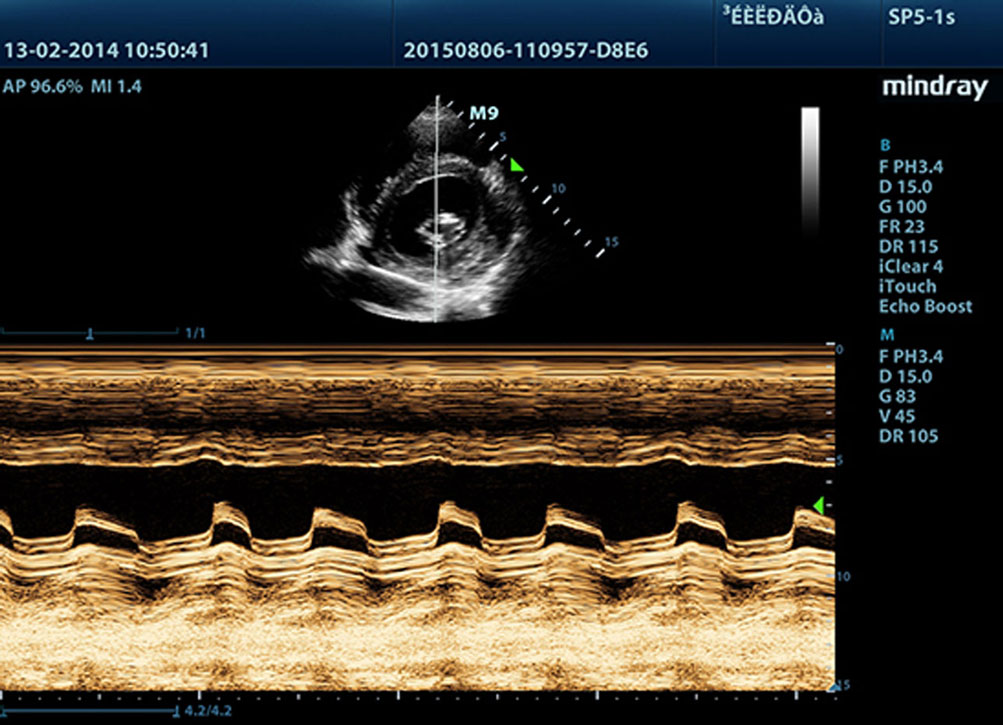

Free Xros M?

Lakukan observasi anatomis yang tepat dengan menempatkan garis sampel di mana pun dengan sudut apa pun. Dapatkan gambar yang lebih baik melalui tampilan berkelanjutan maksimum 3 garis sampel.

Free Xros CM?

Secara akurat mengevaluasi gerakan miokardial dalam berbagai tahap, dan secara terus-menerus melakukan sinkronisasi miokardial. Kecepatan bingkai yang tinggi memberikan hasil yang akurat